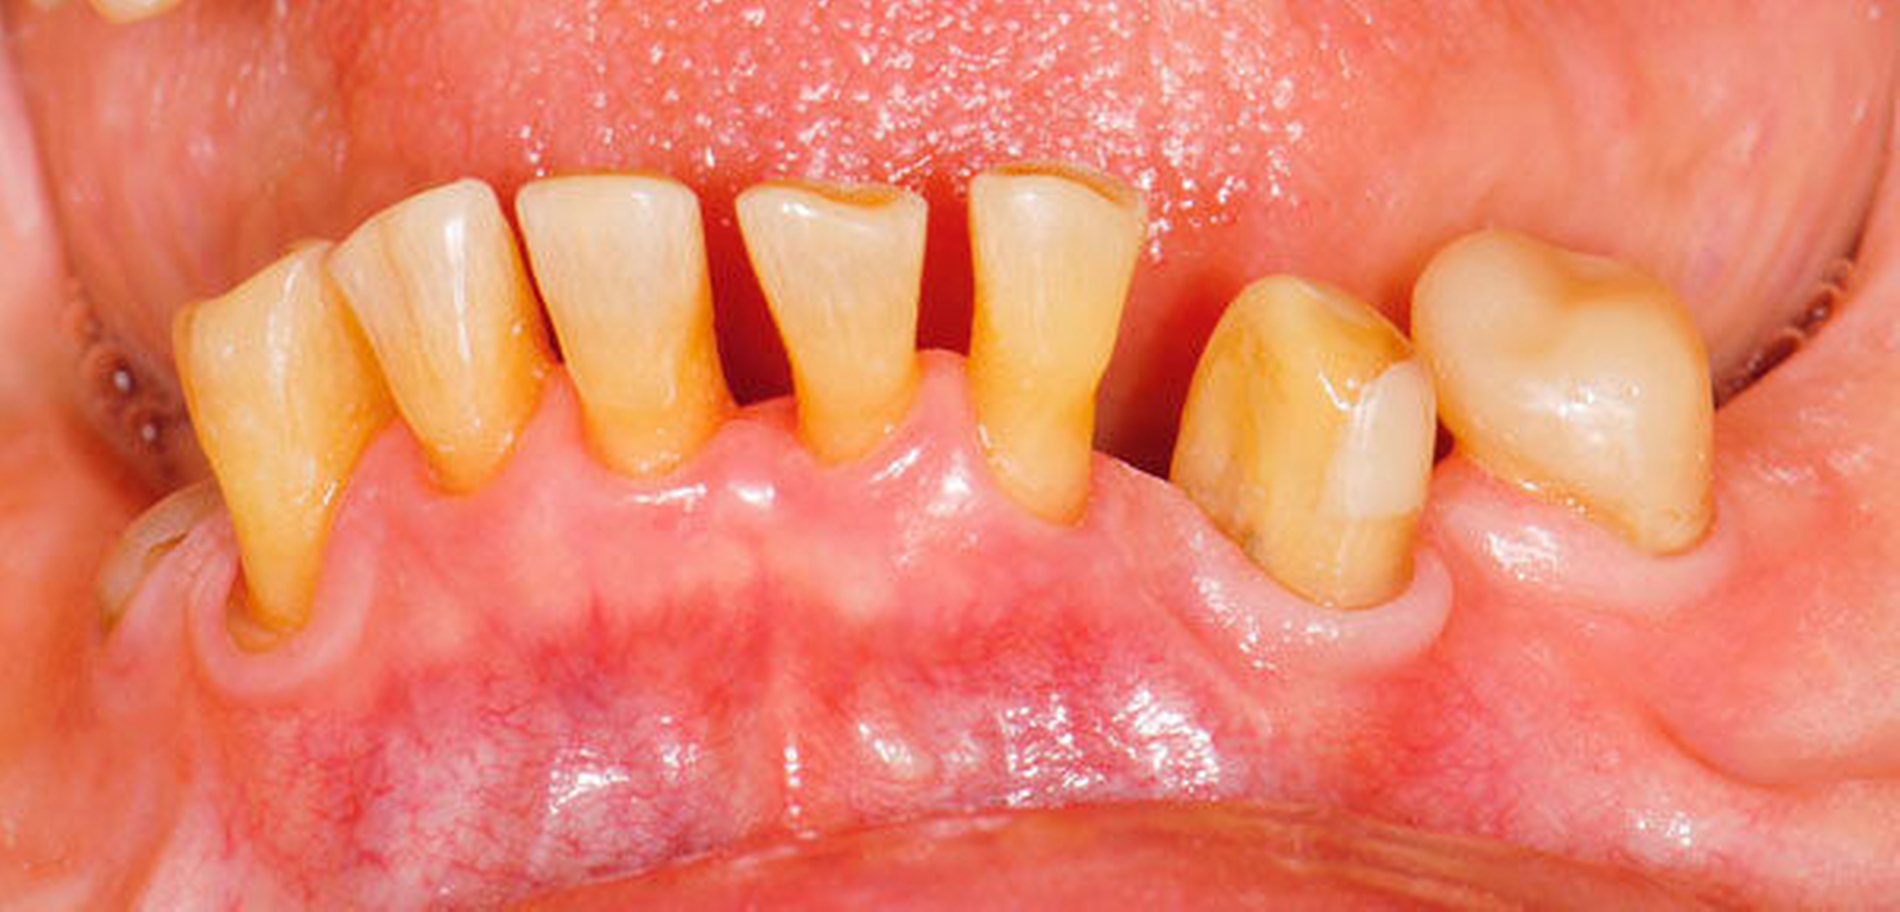

2. Management von Abrasionen, Attritionen und Erosionen

Fast alle bezahnten Senioren weisen deutliche Zeichen von altersentsprechenden Abrasionen, Attritionen und Erosionen auf. Bei langsamer Progression ist in restaurativer Hinsicht meist ein Zuwarten beziehungsweise eine individuelle Prävention indiziert. Bei schneller Progression empfiehlt sich hingegen eine rechtzeitige, teilweise von den Präparationsgrenzen unabhängige „Verschalung“ betroffener Areale mit direkt eingebrachtem Komposit unter Berücksichtigung der Antagonistensituation. Zuweilen müssen unter Abwägung der Vor- und Nachteile scharfe antagonistische Höckerspitzen vorsichtig subtraktiv abgerundet werden, wobei allerdings die Gefahr einer Dentinfreilegung besteht (Abbildung 2, Tabelle 2).

Abbildung 2: 66-jähriger Patient mit ausgeprägten, nicht kariesbedingten Hartsubstanzdefekten an Zahn 37 ohne klinische Symptome: Ob der Zahn jemals mit einer Restauration versorgt war, ist nicht bekannt. Der Patient wünscht an diesem Zahn keine Behandlung.